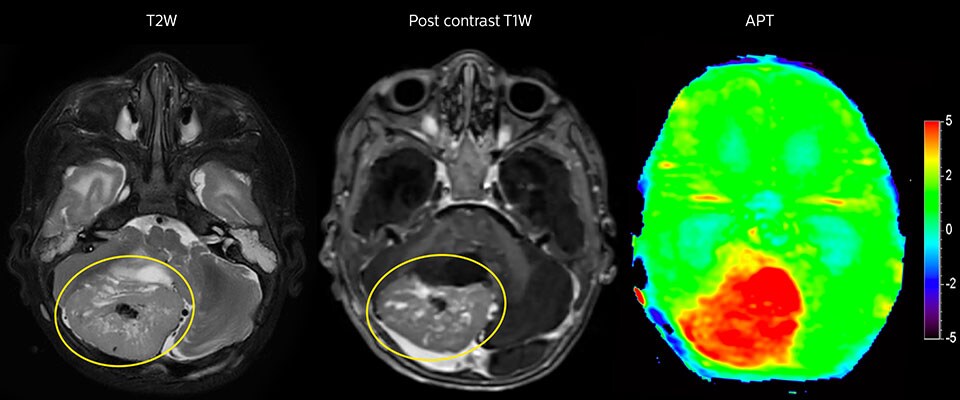

Large metastatic brain lesion

This 10-year-old patient underwent Ewing’s sarcoma tumor resection 7 years ago, but was found to now have a large metastatic lesion in the brain. This lesion shows clearly increased APT signal.

MRI with APT post resection

Immediately post resection MRI was again performed. T2-weighted and postcontrast T1-weighted images are quite inconclusive for distinguishing residual tumor tissue from postoperative tissue changes. On the APT image some high signal is still seen, which would suggest residual tumor tissue.

Follow-up over time

In later follow-up scans the post-contrast T1-weighted images suggest recurrent tumor growth. So, it would be interesting to study the predictive value of APT in a large patient group.